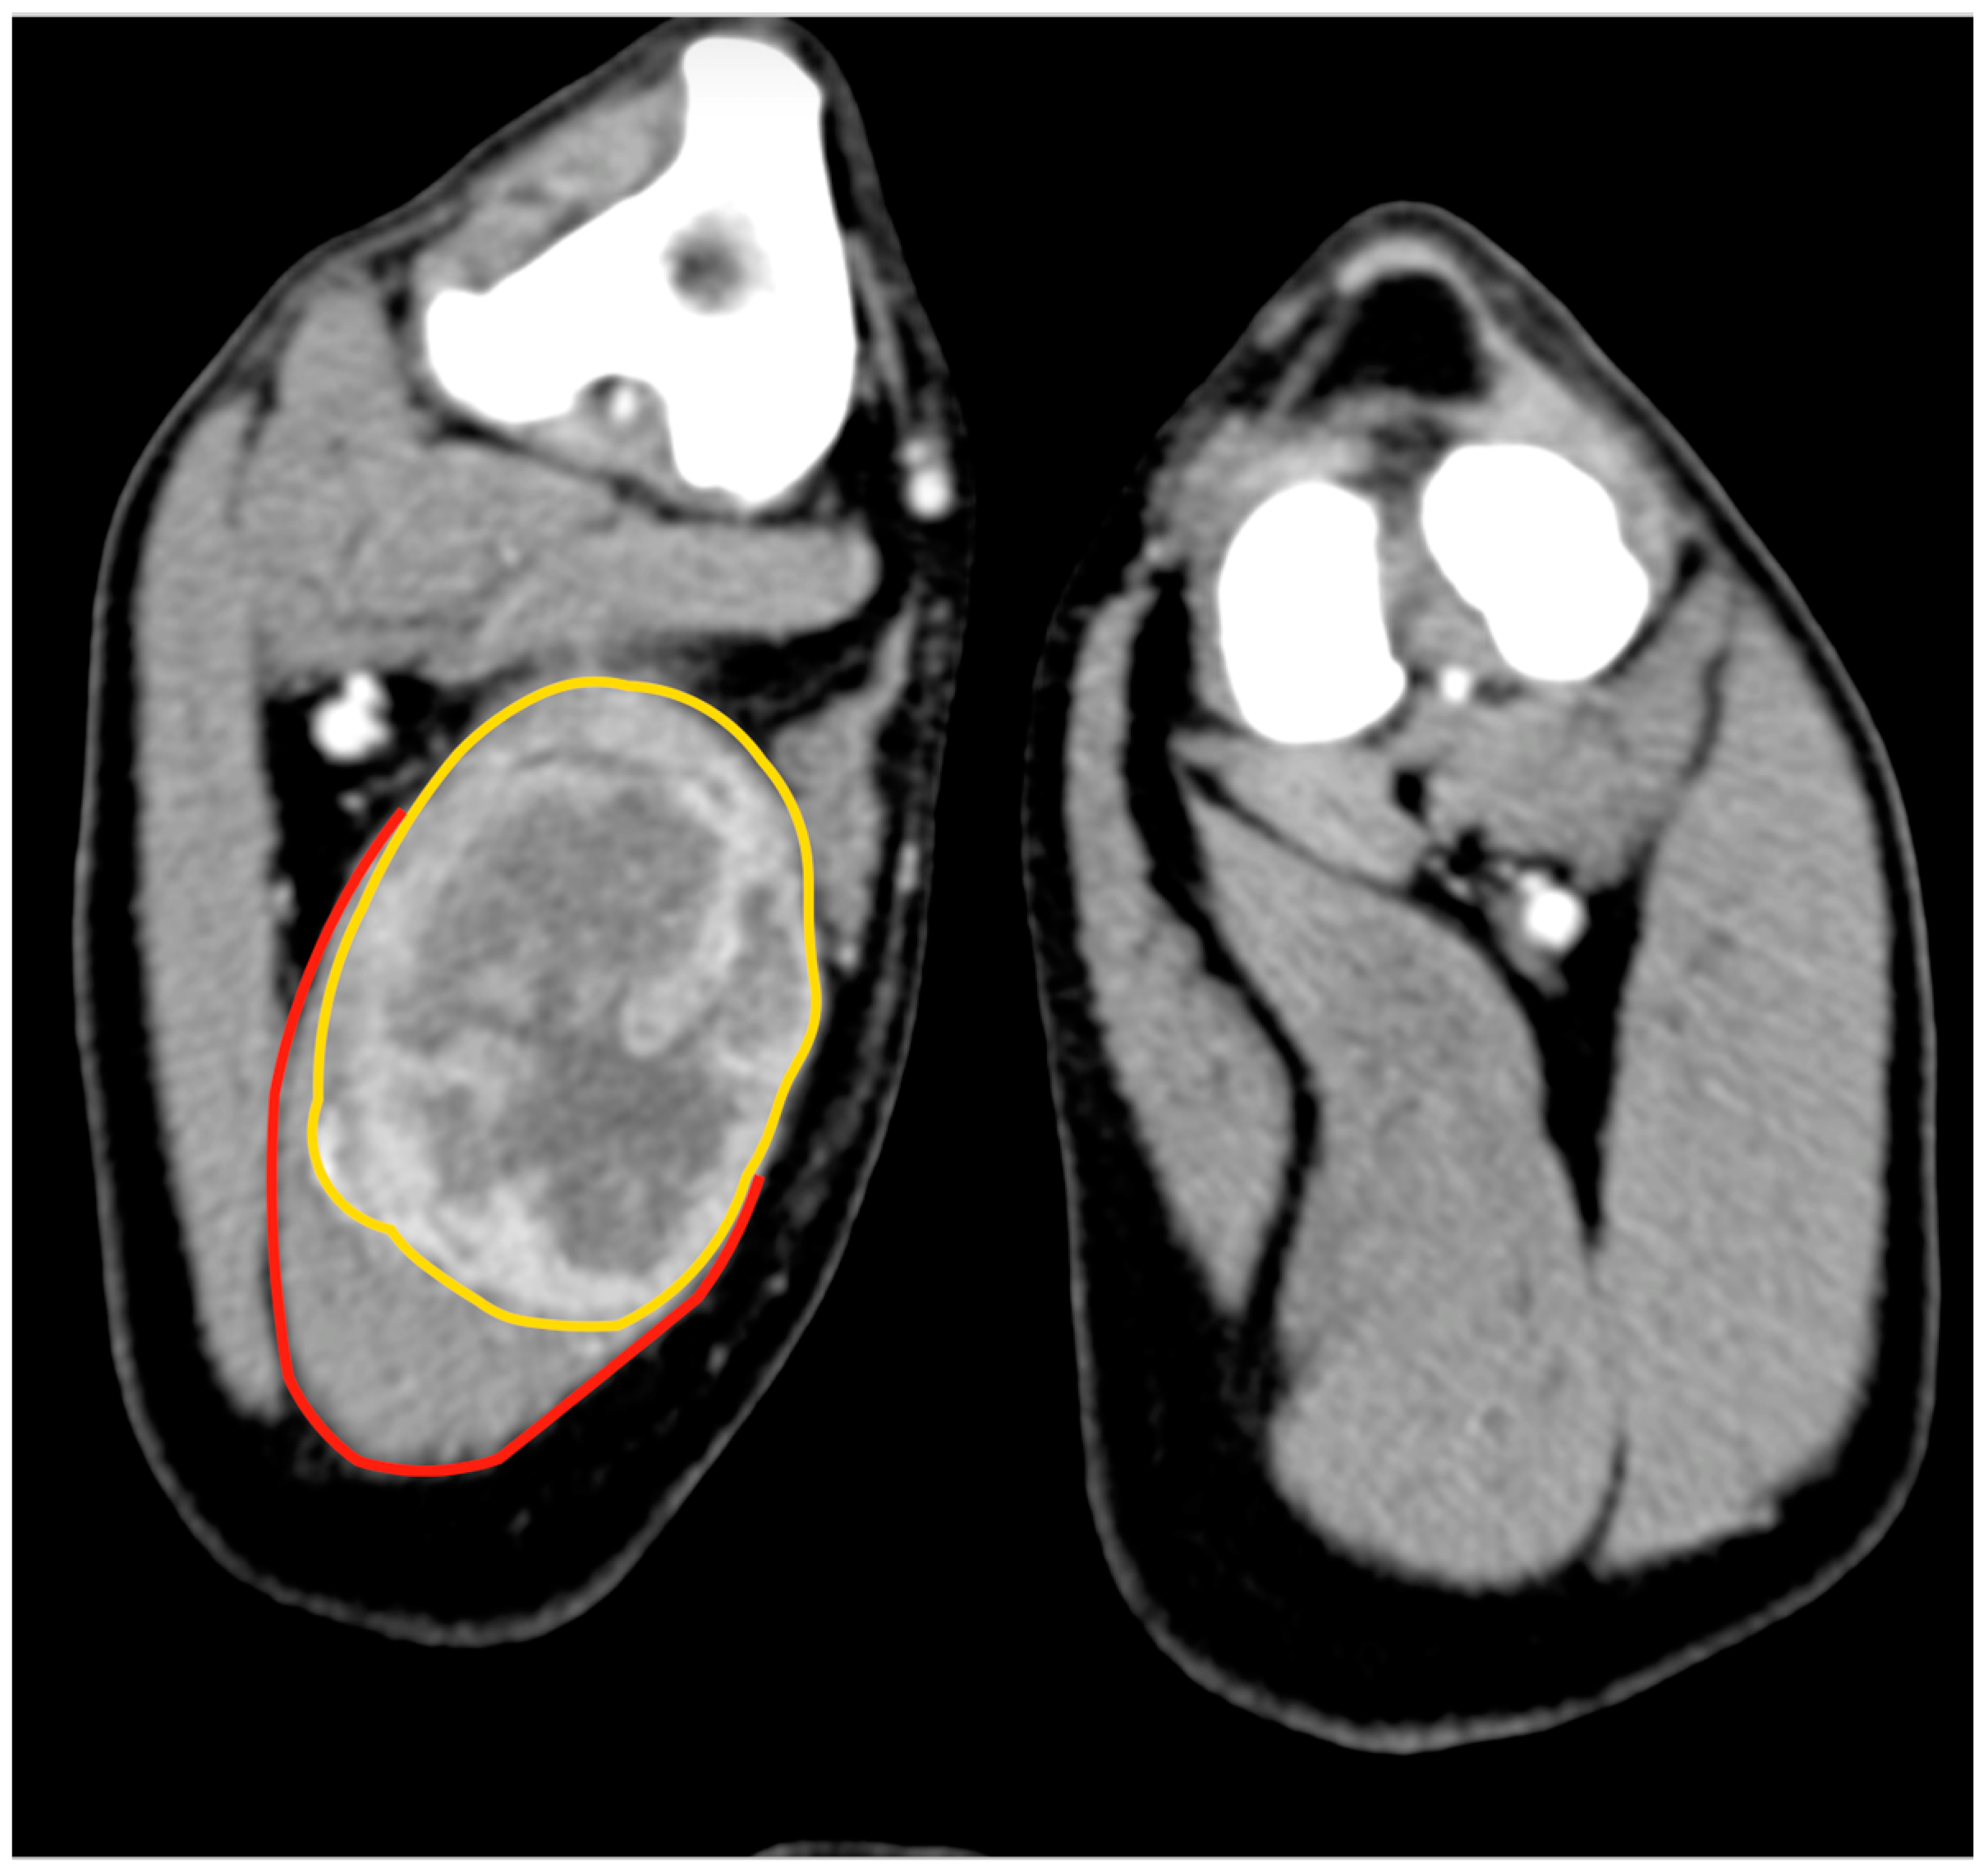

An 11.5-year-old, 28 kg, castrated male Labrador retriever was referred for a 4 cm painless, firm mass in the caudal region of the thigh. The mass had been present for several months but had recently grown. The dog showed no lameness or discomfort. Physical examination and the laboratory profile (complete blood count—CBC, biochemical values and urinalysis) were unremarkable. An incisional punch biopsy was performed during the total body CT exam (Figure 1). The histology was compatible with a soft tissue sarcoma showing chondromyxoid differentiation.

Figure 1.

Tomographic appearance of the neoplasm within the semitendinous muscle. The yellow line delimitates the mass, and the red line is the semitendineous muscle. Orientation: cranial is on the top of the figure.